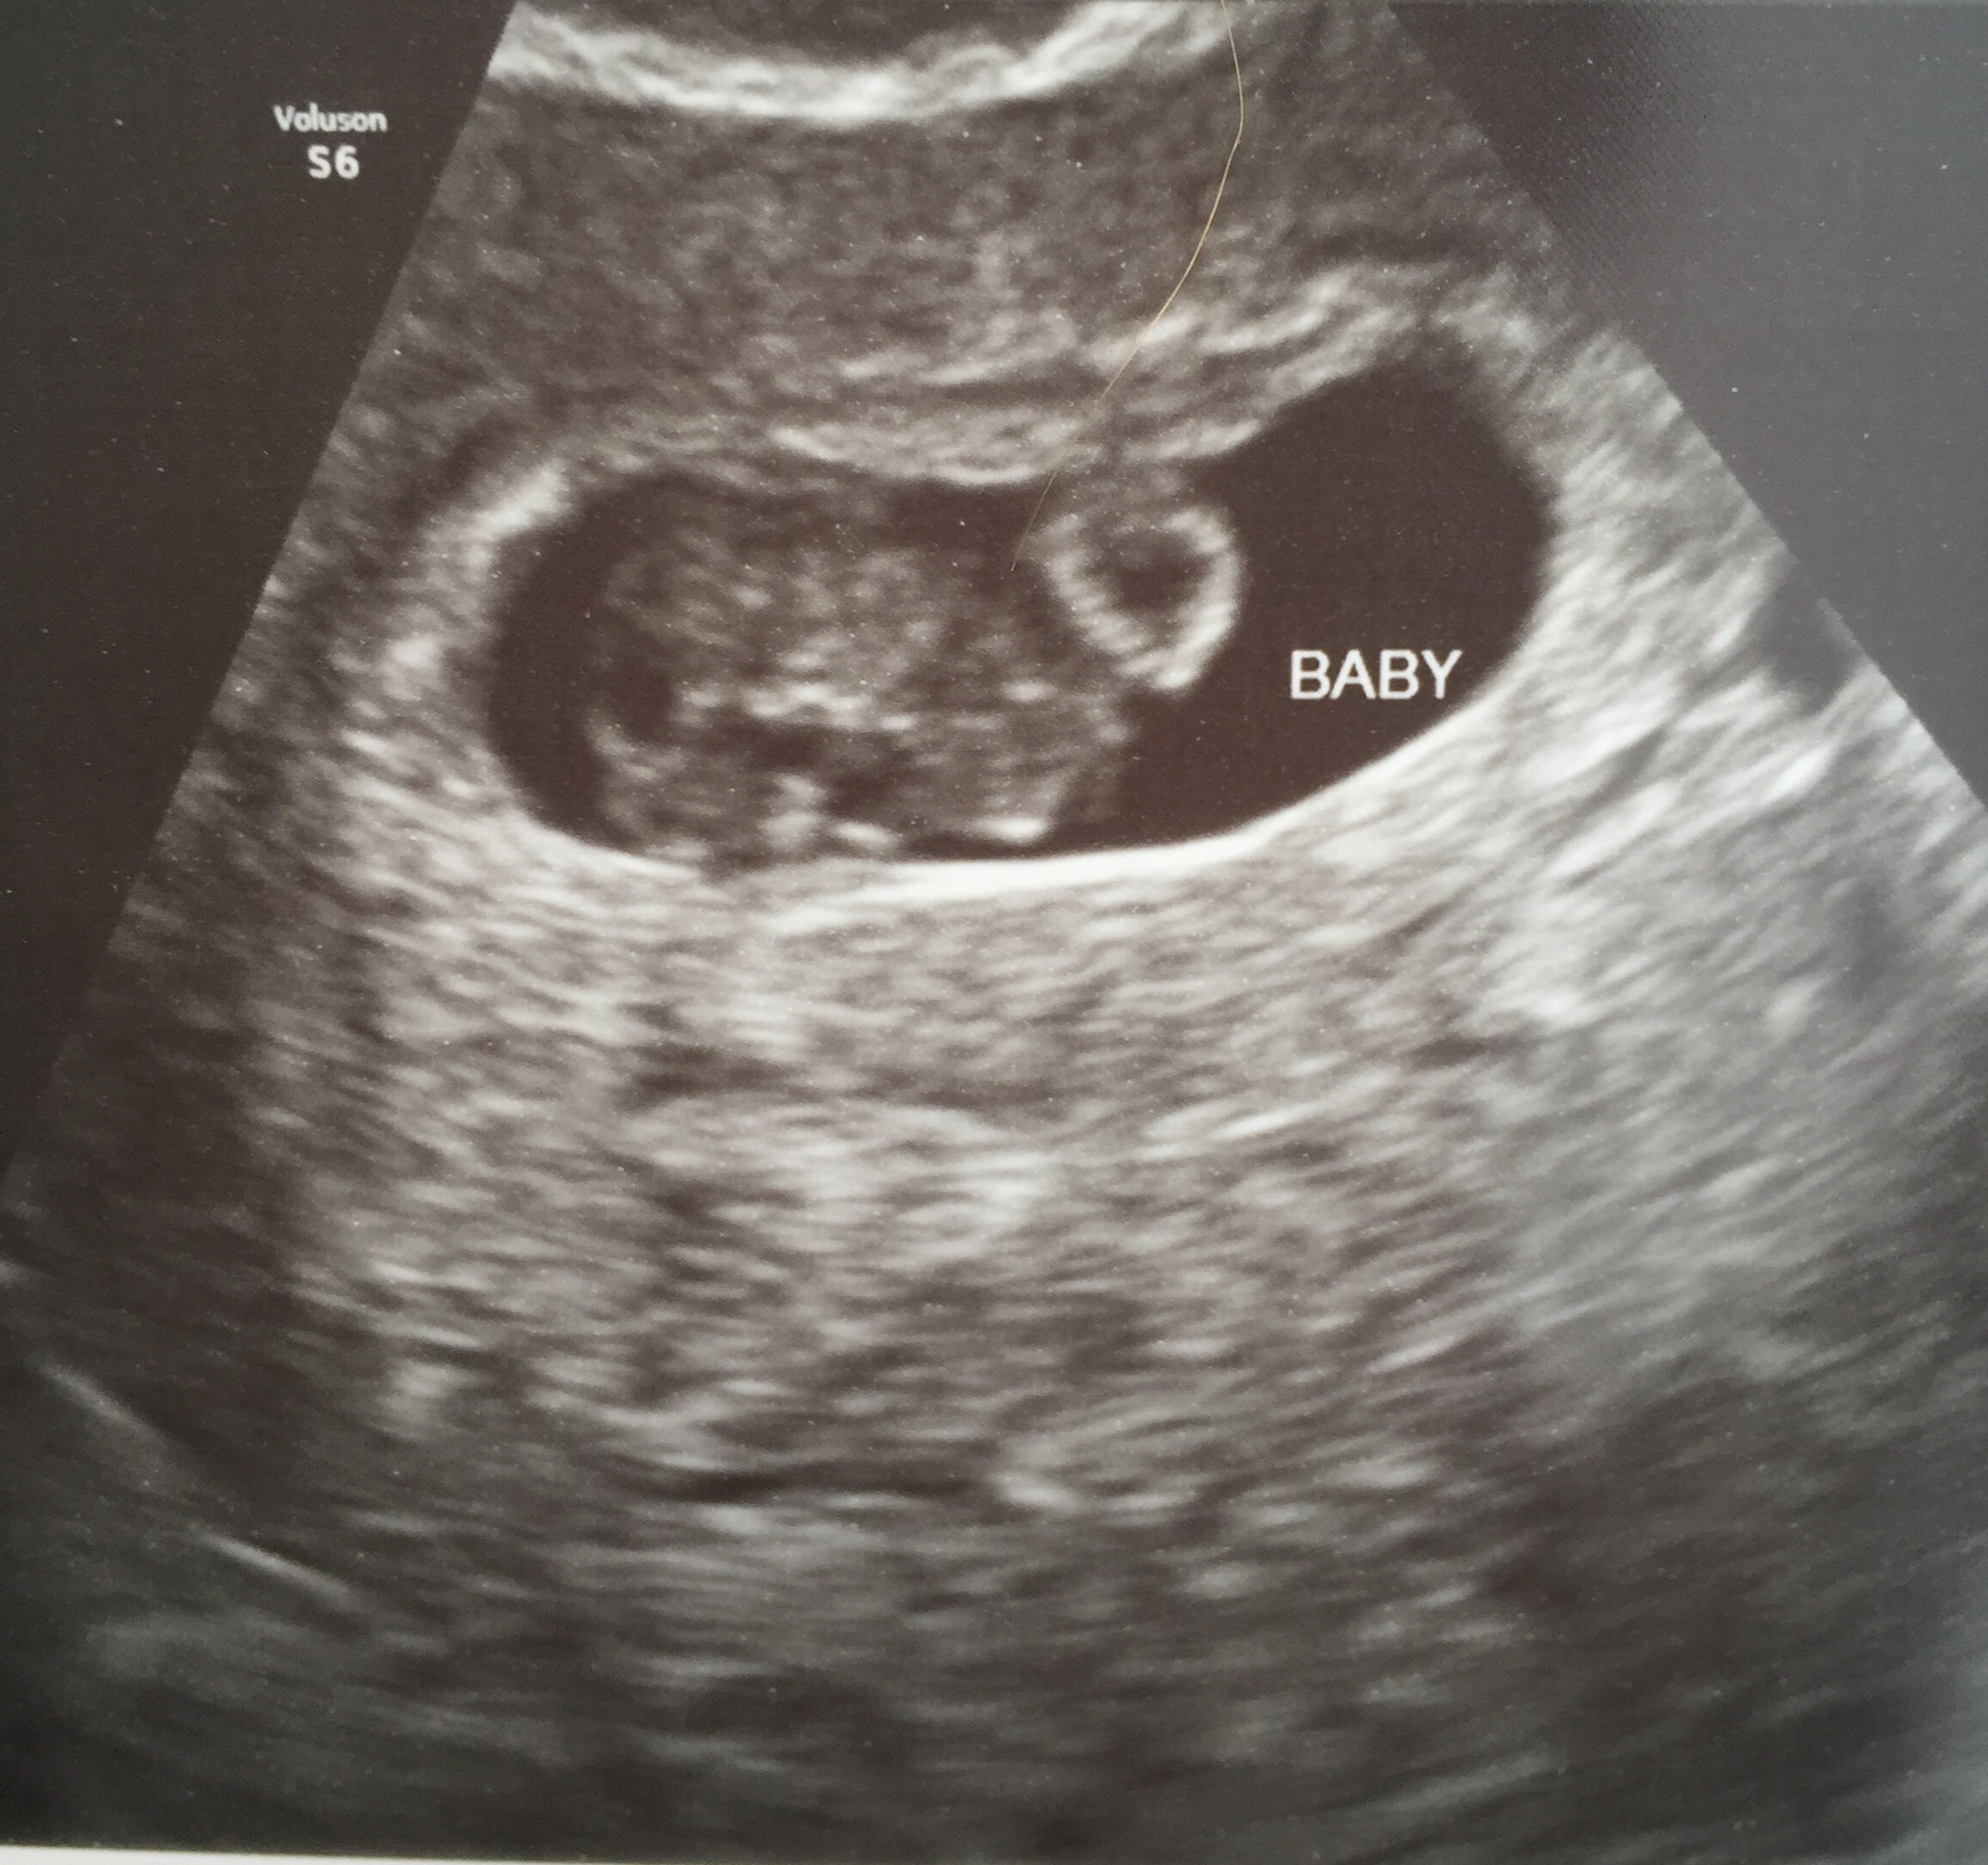

I think I god the shittiest ultrasound as far as clarity goes (and this was the best one! All the others are pretty much all black). To me the sac looks completely vertical with baby at the bottom. So I don't think the Ramzi prediction is going to work for me

Mine is super hard to see, but what do you guys think? It was abdominal and the baby measured 8+6. Is that too late for this "theory"? I will get my blood test results in the next few weeks and am curious about whether they will align.

Is it the side the baby is on or the yolk sac or what? I read the placenta online, but I thought there wasn't placenta yet. My baby is kind of right in the middle but the yolk sac is definitely on the left.